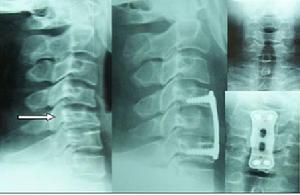

脊柱外科脊柱外科專科特色

從七十年代初開展脊柱傷病的外科治療,每年手術治療脊柱傷病患者300多例,治癒率達95%以上,在套用保守、微創及手術等手段治療頸椎病、腰椎間盤突出、椎管狹窄、脊柱外傷椎體壓縮骨折、腰椎峽部不連、椎體滑脫、椎體轉移腫瘤、脊柱側彎、骨質疏鬆症等方面積累了豐富的經驗。處於國內先進行列。

技術特色:

1、一期後路復位側塊及椎弓根螺釘棒固定+前路減壓植骨融合鋼板內固定治療頸椎骨折並頸椎脫位。

2、前路椎體次全切除,自體髂骨移植鋼板內固定治療頸椎椎體壓縮骨折;前路椎間盤切除移體骨塊移植,鋼板內固定治療頸椎椎間盤突出。

3、後路釘棒系統固定+自體髂骨移植手術治療矯正特發脊柱側彎;椎體截骨+釘棒系統固定矯正脊柱後凸(駝背)畸形。

4、後路減壓枕頸釘棒系統固定+自體髂骨植骨融合術治療陳舊寰樞椎脫位。

5、椎體腫瘤、結核的手術治療。

6、後路釘棒系統固定+自體髂骨移植手術治療腰椎間盤突出、椎體滑脫及椎管狹窄。

7、微創治療腰椎間盤突出症。